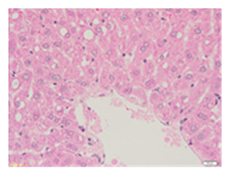

Liver wet weights of all rat groups showed no significant differences (Table 8). According to histochemical hematoxylin and eosin (H&E) staining, treatment with the highest dose of MPE (1000 mg/kg BW) did not result in morphological changes in the liver tissue (B) when compared with DI water treatment (A). Obviously, CCl4 induction (ip)/DI water treatment (po) caused hepatoxicity, which was indicated by a severe degree of fatty changes and fatty cysts in the liver tissue (C), whereas pretreatments of silymarin (100 mg/kg BW, po) effectively decreased the degree of fatty changes and fatty cysts in the liver when compared with the CCl4/DI water group. Indeed, MPE (250 and 1000 mg/kg BW, po) lowered the degree of lipid accumulation in the liver; inversely, MPE (500 mg/kg BW, po) exhibited a severe degree of lipid accumulation. Apparently, taking paracetamol (2 g/kg BW) induced a severe degree of hepatic necrosis when compared with rats that had not received the treatment. Similarly, pretreatments of silymarin (100 mg/kg BW, po) and MPE (250 and 1000 mg/kg BW, po) revealed a mild degree of hepatic necrosis, while MPE (500 mg/kg BW, po) revealed a moderate to severe degree of hepatic necrosis. Accordingly, the findings imply that the consumption of MPE (1000 mg/kg BW) was not harmful to the liver of healthy rats, while MPE (250 mg/kg BW) did improve fat deposition in the livers of CCl4-fed rats and offered protection against liver cell damage in paracetamol-fed rats.

Wet weight values (mean ± SD) and H&E staining of liver from rats with hepatotoxicity induced by CCl4 and paracetamol.